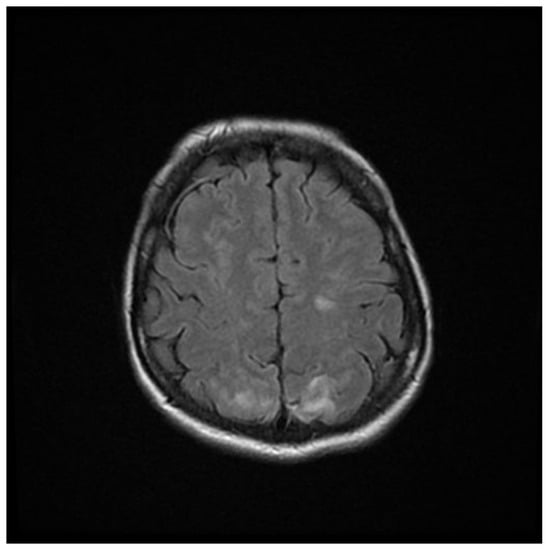

Computed tomography (CT) angiography of the head and CT with contrast were performed and excluded aneurysm, arteriovenous malformation (AVM), dural sinus thrombosis, and tumor. Due to the lack of deviations in the previous tests, an MRI of the head with contrast was performed, in which small areas and hyperintense bands in the T2-weighted image (T2-WI) and Fluid Attenuated Inversion Recovery (FLAIR) were visualized on both sides in the parieto-occipital areas without either diffusion restrictions or contrast enhancement, a typical manifestation of PRES [4], as shown in Figure 1, Figure 2, Figure 3 and Figure 4.

Figure 3. T2-WI MRI sequence of the brain in transverse plane.